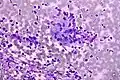

Colorectal adenocarcinoma. Field stain. -

Granuloma. Field stain.